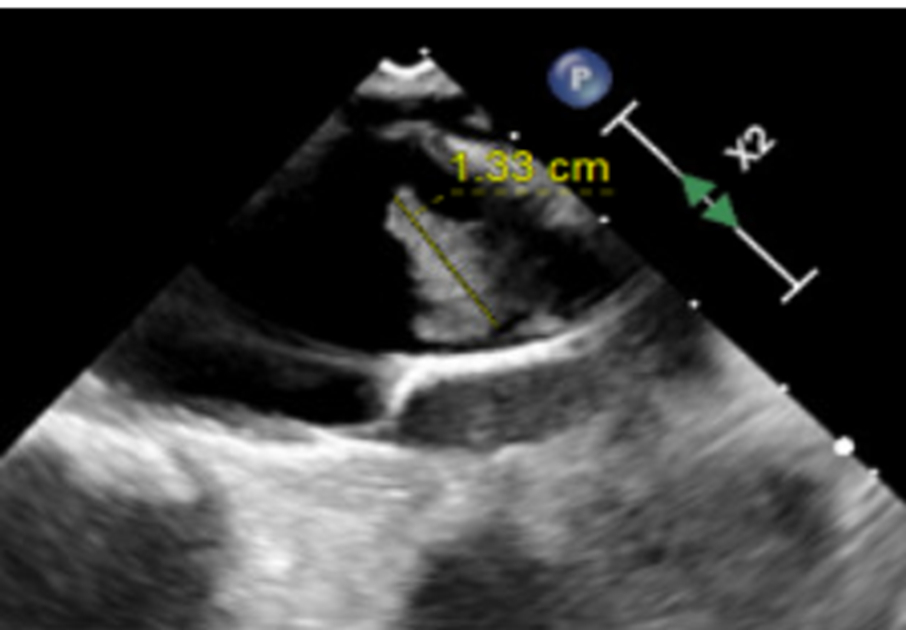

Initial work up